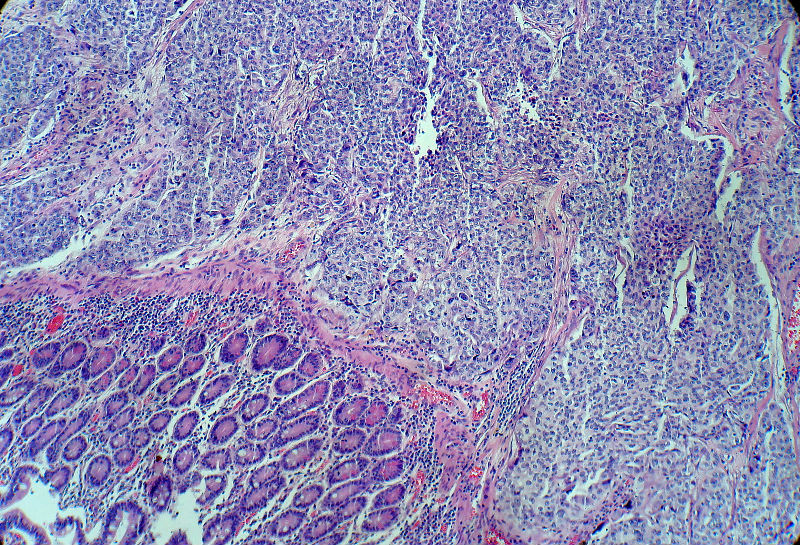

男,82岁,小肠穿孔紧急手术。

大体,小肠一段,长约60厘米,与粘膜面可见三个溃疡型肿物,肠系膜淋巴结肿大。

肿瘤呈巢片状分布,细胞大小相对一致,胞浆丰富,胞核呈细颗粒状,可见小核仁,血管较丰富,考虑神经内分泌肿瘤,加做免疫组化(Ki67、Syn、NSE、CgA、CD56)分级。

肠系膜淋巴结

神经内分泌肿瘤,加做免疫组化(CKp、Ki67、Syn、NSE、CgA、CD56)分级。